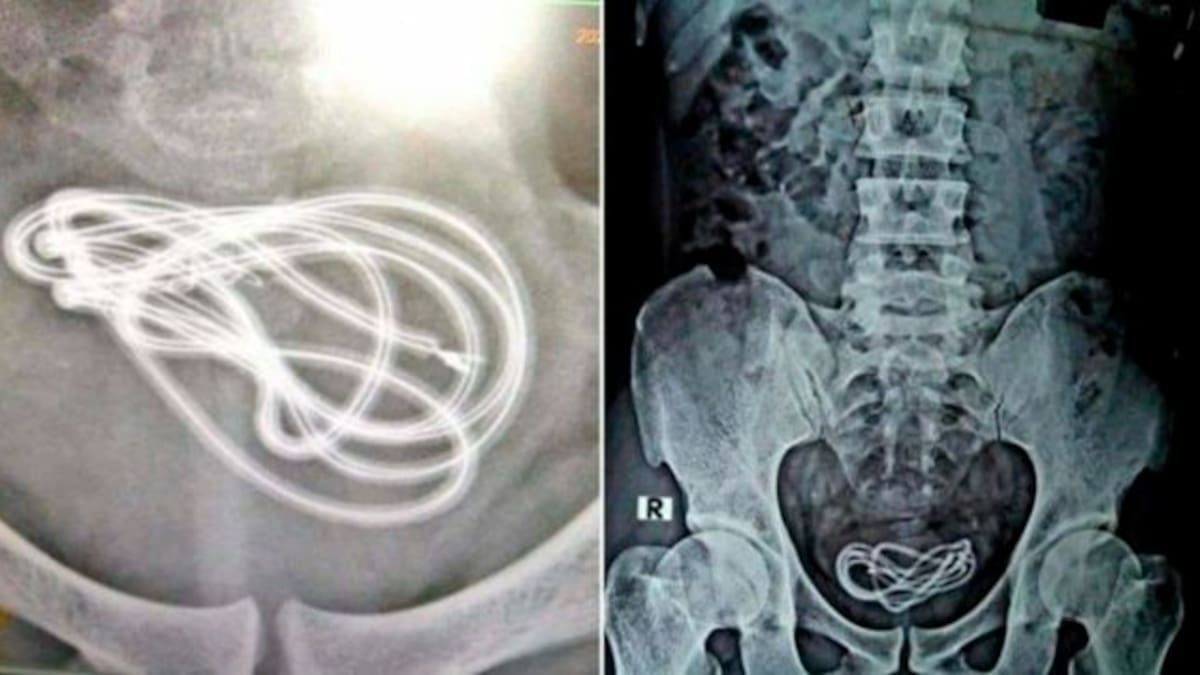

El hombre estaba experimentando con el cable y terminó en el hospital